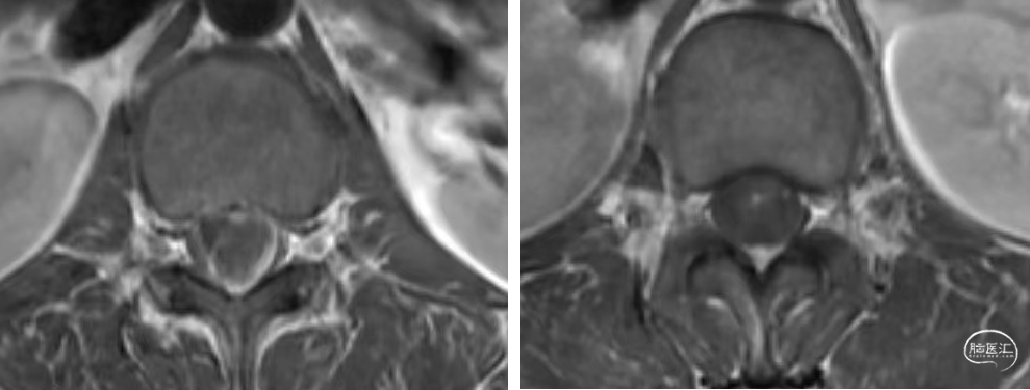

辅助检查:腰椎CT和MR示:L1-2椎管内硬膜下见一软组织信号结节,大小约24mm×12mm×10mm,T1W1低信号,T2W1稍高信号,增强扫描明显强化,但欠均匀,临近脊髓受压改变等。

术前腰椎CT和MR如下: